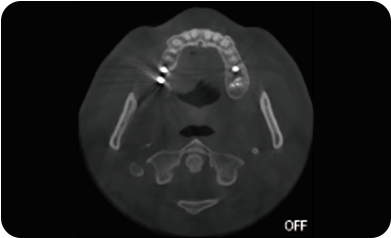

局部超清显示、 移动视野摄片

可根据临床需求任意调整成像区域大小实现局部超清三维显示

临床样片